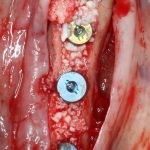

Откроем область операции и посмотрим, что там:

Вроде как, всё неплохо. Наверное, можно поставить имплантаты?

ну, или как-то так:

При этом, я хотел бы обратить ваше внимание на один важный момент. То, с чем вы сейчас работаете — не кость, в привычном нам гистолого-физиологическом понимании. Это костная мозоль вперемежку с графтом. Её свойства довольно сильно отличаются от того, что мы привыкли называть костной тканью. Поэтому при установке имплантатов соблюдайте максимальную осторожность и щадящий режим. Никаких диких торков, усилий, больших переходов между размерами фрез допускать нельзя. Будьте аккуратны.